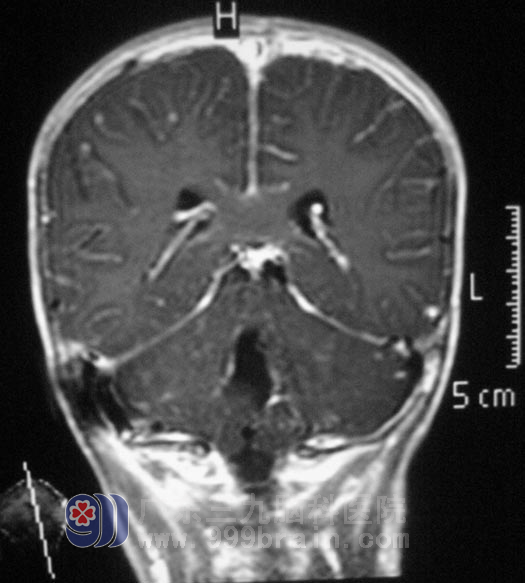

十天前,思思偶有呕吐伴有全身乏力,并出现走路不稳,家人这才慌了神,在当地医院就诊,头颅CT示:四脑室后方巨大占位,性质待定。http://www.999brain.com/

广东三九脑科医院MR检查提示病变范围约5.04cm×3.31cm×4.12cm,脑干受推压、前移,桥前池边窄,初步考虑髓母细胞瘤。